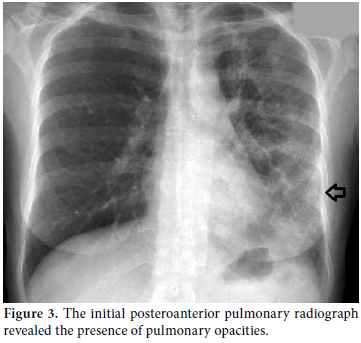

Consultations were then held with the pulmonary medicine and rheumatology departments regarding the eosinophilia identified in the CBC, pulmonary opacities revealed via chest X-ray, and the patient's past history of asthma (Figure 3). Furthermore, cranial computed tomography (CT) was performed on the day after the angiography which showed neurological involvement or paranasal sinus abnormality with a prediagnosis of CSS. The results of the cranial CT were also consistent with chronic sinusitis. The presence of asthma, hypereosinophilia of >10%, chronic sinusitis, and pulmonary opacities represent four of the six ACR criteria required for the diagnosis of CCS.[5] Our patient tested negative for anti-nuclear antibodies (ANAs), anti-double stranded DNA (antidsDNA), extractable nuclear antigens (ENAs) and anti-neutrophil cytoplasmic antibodies (ANCAs). The corticosteroid methylprednisolone at an initial dosage of 80 mg per day (1 mg/kg/d) was prescribed after the termination of the tirofiban infusion. Afterwards, the patient's eosinophil levels in the CBC decreased to normal ranges, and symptomatic relief was completely provided. Control coronary angiography was performed one week later, and the thrombotic lesions had disappeared (Figure 4). In addition, chest radiographs showed complete resolution of the opacities (Figure 5). After two more weeks, control echocardiography was performed revealing a normal morphology of the ventricles without any segmental wall motion abnormalities. Furthermore, the pericardial fluid had also disappeared.